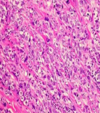

Stomach, Signet Ring Carcinoma

Invasion by MALIGNANT TUMOR composed of signet ring cells. These cells are poorly cohesive and have clear cytoplasm with dark eccentric nuclei

Malignant

Signet ring cells

Due to cytoplasmic mucin pushing nucleus to side